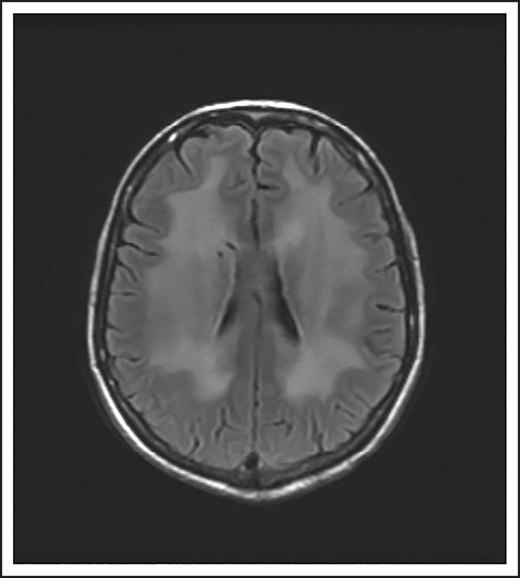

A 74-year-old man with a history of DLBCL treated with R-CHOP presented with progressive confusion and right-side weakness. A brain MRI demonstrated a contrast-enhancing lesion in the corpus callosum with extension into the left parietal region. A biopsy of the enhancing lesion confirmed a diagnosis of DLBCL. No other sites of disease were identified, and he was diagnosed with isolated CNS relapse. He was treated with HD-MTX, rituximab, and temozolomide for 4 cycles, and he achieved a complete radiographic response. Three years later, he presented with progressive memory loss, urinary incontinence, and gait ataxia. A brain MRI demonstrated periventricular white matter T2/FLAIR hyperintensities (Figure 3). Evaluation for toxic and metabolic causes of his symptoms was negative. His diagnosis was MTX-induced leukoencephalopathy.

Brain MRI of a patient with leukoencephalopathy caused by use of HD-MTX. An axial T2 fluid attenuated inversion recovery (FLAIR) image shows periventricular hyperintense signal reflecting leukoencephalopathy.